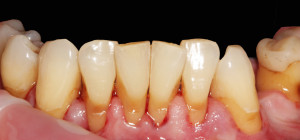

Widać wyraźnie, że kamień i gruba warstwa płytki bakteryjnej wywołał stan zapalny dziąseł – są przekrwione, i opuchnięte. Higienistka wykonała skaling naddziąsłowy skalerem EMS, wypiaskowała zęby piaskiem Air-Flow Plus oraz wypolerowała pasta polerską. Po zabiegu różnica wyglądzie zębów jest diametralna: zdjęcie 2, zdjęcie 5.

Naszym celem jednak jest nie tylko ładny wygląd zębów ale wyleczenie stanu zapalnego dziąseł, a to nie będzie możliwe bez dokładnego wyedukowania pacjenta. Higienistka przeprowadziła szczegółowy instruktarz prawidłowej metody szczotkowania – pokaz na modelu i samodzielna próba pacjenta na własnych zębach. Pacjent nauczył się również stosowania szczoteczek międzyzębowych, będących w jego przypadku niezbędnym akcesorium higienicznym ze wglądu na szerokie przestrzenie miedzyzębowe. Zalecone zostały środki pomocnicze – Eludril do płukania, pasta Elgydium Anti-Pacjent spotkał się z nasza higienistka jeszcze dwa razy, w celu dokonania kontroli i ewentualnego doczyszczenia. Na drugiej wizycie kontrolnej dziąsła pacjenta wyglądały tak: zdjęcie 3, zdjęcie 6. Komentarz jest chyba zbędny: różnica widoczna gołym okiem, dziąsła są zdrowe, bladoróżowe, bez opuchlizny. Gratulujemy!!!